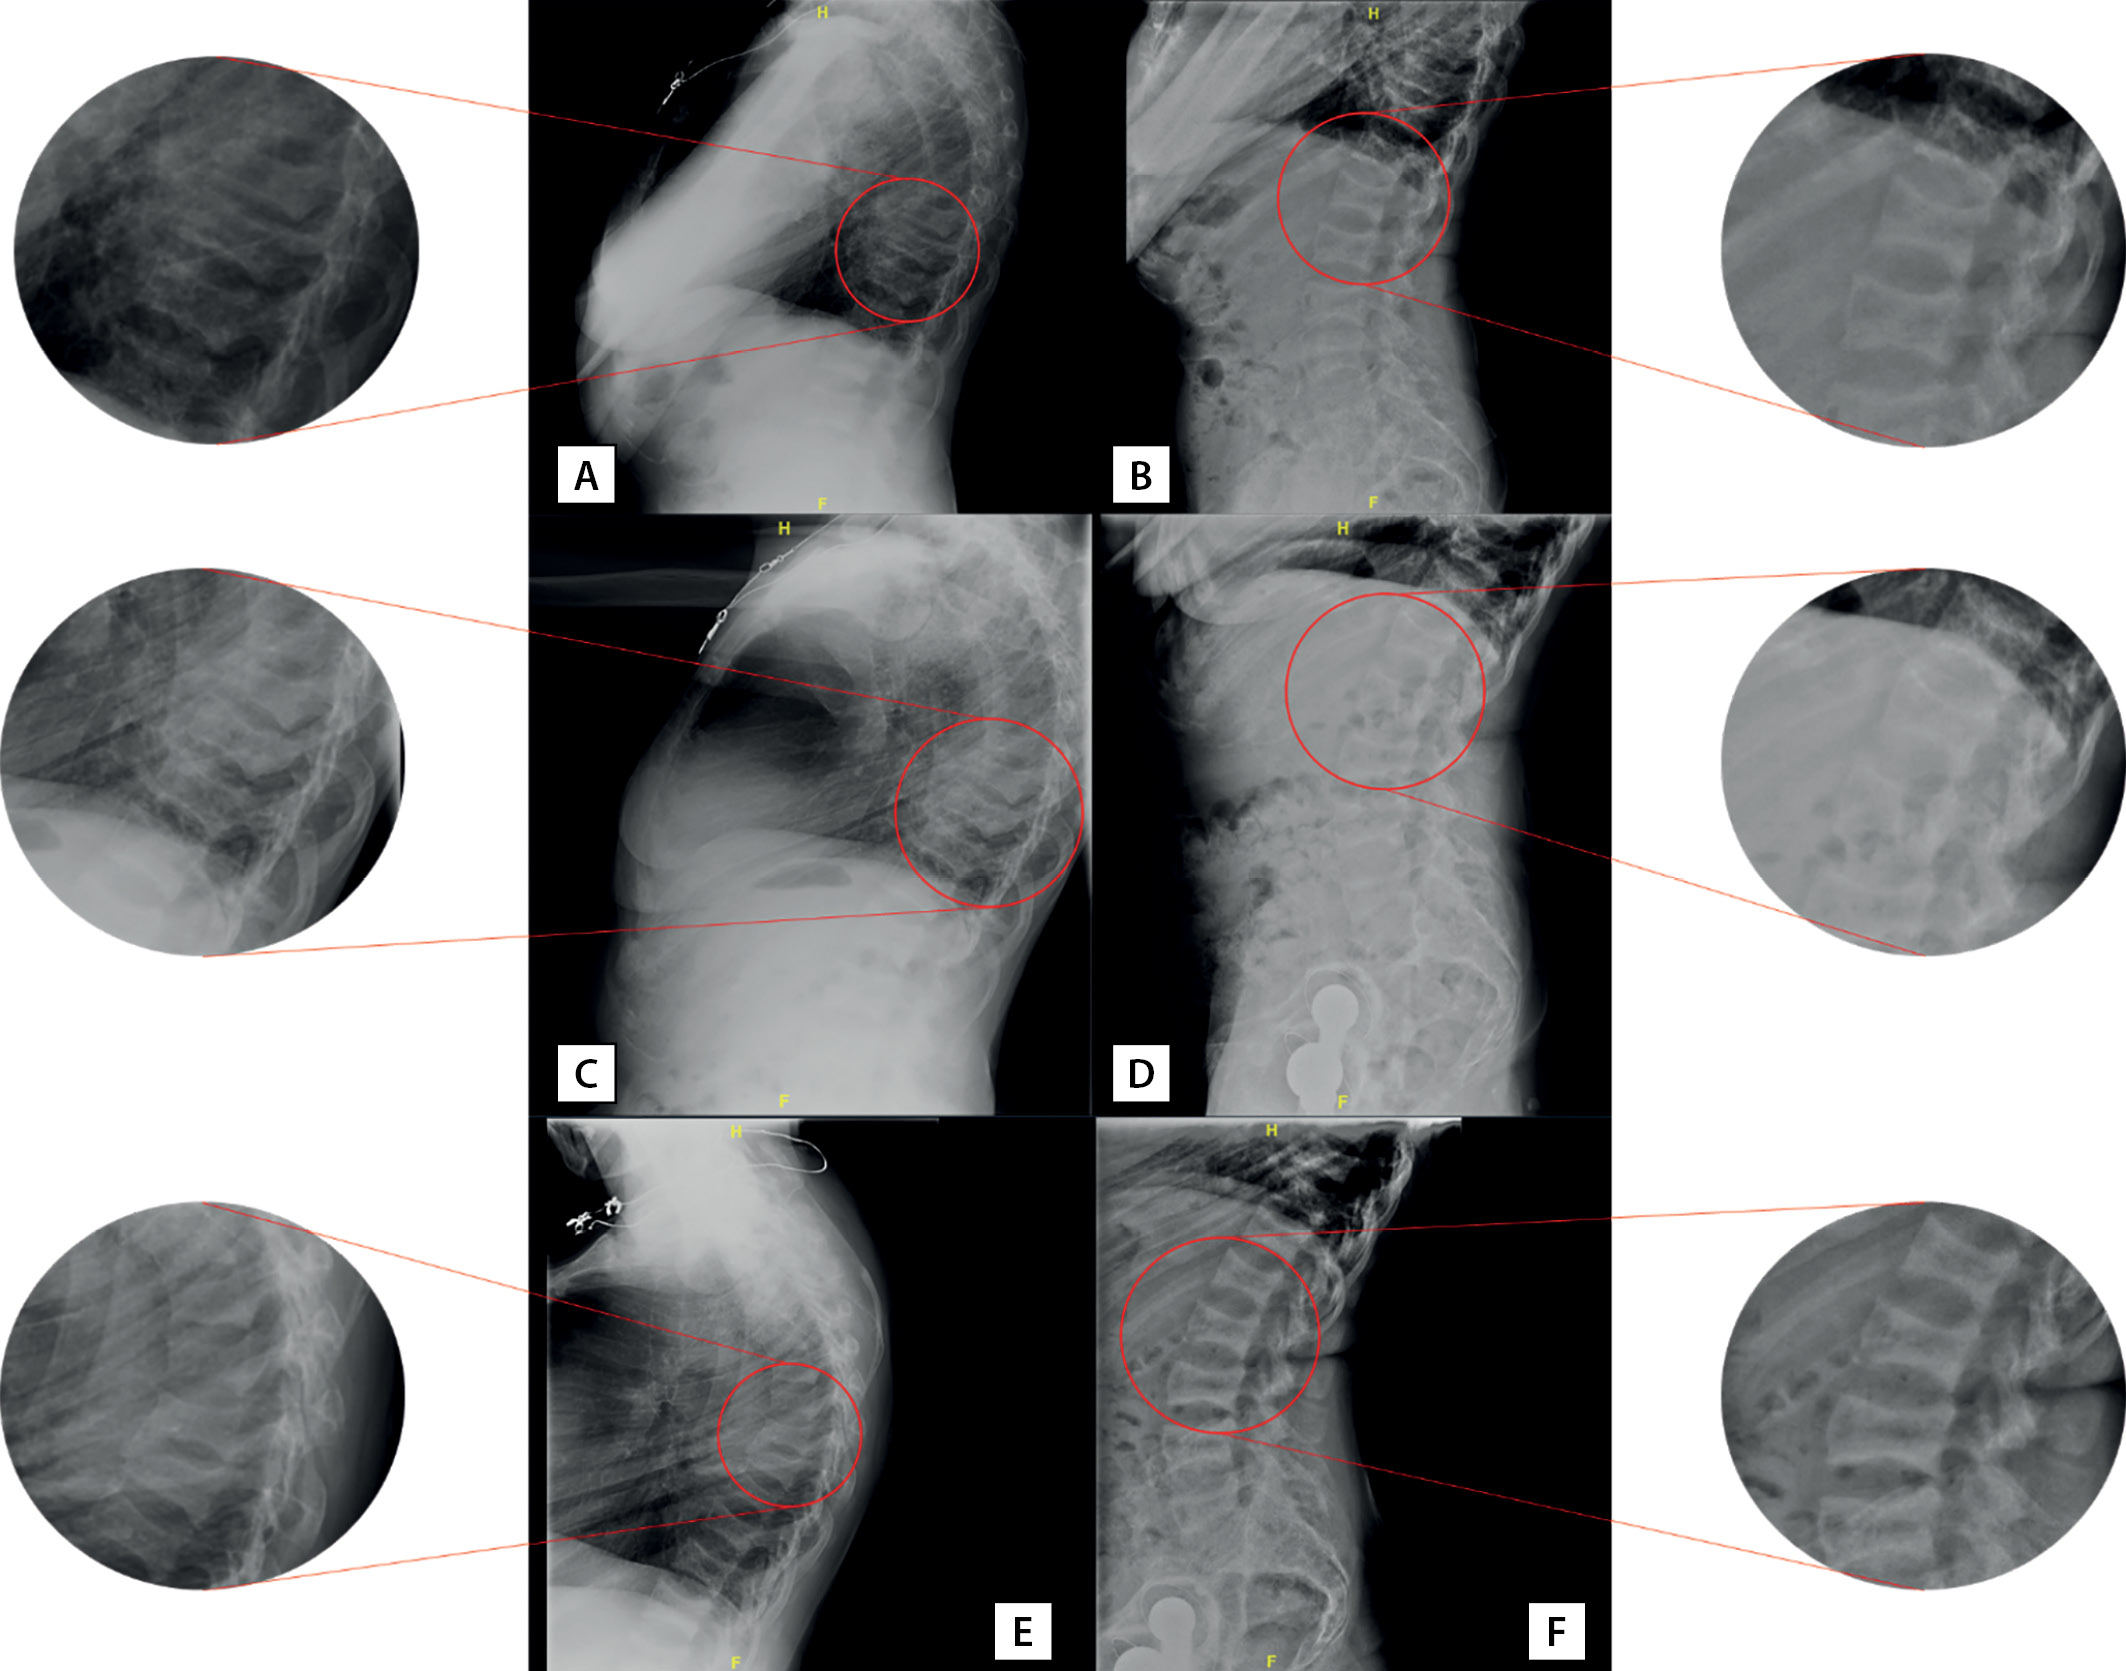

При госпитализации в 2018 г. установлен диагноз хронического гипопаратиреоза в стадии декомпенсации (альбумин-скорректированный кальций 1,65 ммоль), снижение сывороточной концентрации ПТГ сохранялось и после перевода пациентки нагемодиализ с концентрацией кальция в диализирующем растворе 1,25 ммоль/л. При рентгенографии грудного и поясничного отделов позвоночника в боковой проекции в июле 2018 г. выявлена деформация по типу «рыбьих» позвонков, компрессионные переломы тел ThX (35% потери МПК), ThIX (40%), ThVIII (65%), ThVII (68%) позвонков и потеря МПК в задних третях тел поясничных позвонков максимально до 37% (рис. 2 А, В).

Рисунок 2. Рентгенография позвоночника пациентки А.: грудной (А, C, E) и поясничный (В, D, F) отделы в боковых проекциях. А и В — июль 2018 г., C и D — сентябрь 2019 г., Е и F — сентябрь 2020 г. Пояснения в тексте.

Figure 2. X-ray of patient A’s spine: thoracic (A, C, E) and lumbar (B, D, F) sections in lateral views. A and B — July 2018, C and D — September 2019, E and F — September 2020. Explanations in the text.

Осенью 2019 г. при рентгенографии грудного и поясничного отделов позвоночника в боковой проекции определялись компрессионные переломы c ThVI до ThX (15–29% потери массы, преимущественно вентрально/каудально), LIII и LV (25–30% потери массы в дорсальных третях позвонков) (рис. 2 С, D). По результатам эхокардиографии 01.10.2019 определялись признаки кальцификации кольца и створок аортального и митрального клапанов. Ранее эхокардиография пациентке не выполнялась.

По результатам рентгенденситометрии сохранялась положительная динамика прироста МПК в лучевой кости (см. табл. 4). Обращал на себя аномальный прирост МПК в поясничном отделе позвоночника. При контрольной рентгенографии отмечено снижение высоты тел ThXII (16% потери массы), ThXI (14%), ThX (23%), ThIX (20%), ThVIII (49%), ThVII (45%), ThVI (43%), ThV (44%), LV (32%), LIV (26%), LIII (22%), LII (18%), LI (15%) позвонков (рис. 2 Е, F). Однако на рентгенограммах отмечалось появление симптома «сэндвича» (или «джемпера регбиста») — значимое утолщение кортикального слоя в телах позвонков. С одной стороны, была отмечена отрицательная динамика в виде появления дополнительного снижения высоты тел ранее поврежденных и прежде интактных позвонков. С другой стороны, учитывая выраженную кифотическую деформацию позвоночника пациентки, указанные изменения могли быть следствием как усиления степени кифоза, так и боковой ротации отдельных позвонков. По решению врачебной комиссии в связи с отсутствием альтернативных методов лечения остеопороза у данной пациентки рекомендовано продолжить инъекции терипаратида в течение последующих 6 мес (до достижения суммарного срока в 2 года).